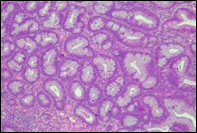

The present study concluded that, out of the total 77 patients with colorectal neoplasia, 17 (22.1%) had a high degree of differentiation (G1), 51 (66.2%) had a moderate degree of differentiation (G2), and 9 (11.7%) had a low degree of differentiation (G3). Figure 3 illustrates the different morphopathological forms of colorectal neoplasia observed in the patients included in the study.

A | B |

C | |

Fig. 3 Morphopathological forms of colorectal tumors (degree of differentiation) A – conventional highly differentiated colonic adenocarcinoma (G1) (HE stain, ×200) B – moderately differentiated (G2) conventional colonic adenocarcinoma (HE stain, ×200) C – conventional poorly differentiated colonic adenocarcinoma (G3) (HE stain, ×200) | |